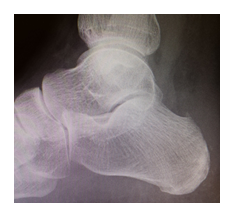

Haglund Exostose

Bei der Haglund Exostose handelt es sich um einen knöchernen Überstand der Ferse, was zu einer Bedrängung der Achillessehne führen kann. Ein Schleimbeutel schützt die Sehne davor, an diesem knöchernen Überstand „zerrieben“ zu werden, wobei er sich meist schmerzhaft entzündet und dabei anschwillt. Daher haben die Patienten nicht nur Probleme beim Gehen, sondern auch durch Druck des Schuhs auf den entzündeten Schleimbeutel.

Wenn trotz Schonung und ggf. Physiotherapie keine dauerhafte Besserung eintritt, sollte der knöcherne Überstand abgetragen und der schmerzhafte Schleimbeutel entfernt werden. Die Patienten müssen nach der Operation für drei Wochen an Stützen entlasten und eine spezielle Schiene tragen. Danach ist im Normalschuh die Vollbelastung erlaubt. Es dauert jedoch noch weitere 4-6 Wochen, bis die Beschwerden abgeklungen sind. Wenn der Patient im Alltag beschwerdefrei ist, kann auch allmählich wieder mit Sport begonnen werden. Dieses ist meist bei Kontakt-/Laufsportarten 3-4 Monate nach der OP möglich, Schwimmen und Radfahren oftmals schon vorher.